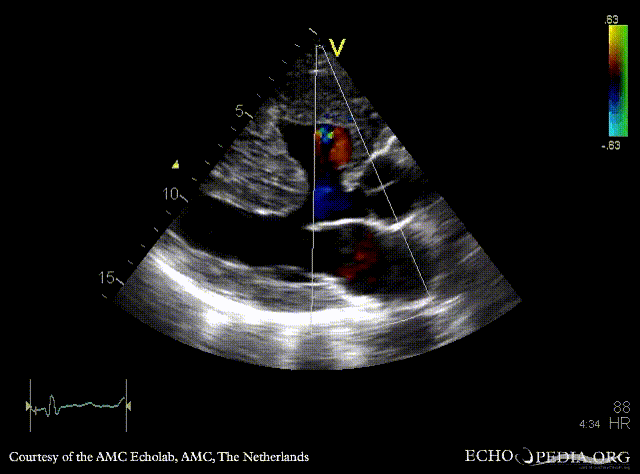

Large VSD, syndrome of Eisenmenger

PSAX: Color Doppler of large VSD

A4CH

A4CH: Color Doppler